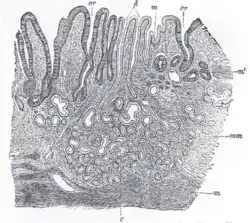

Section of duodenum of cat. X 60. (Muscularis mucosae labeled at right, third from the top.)

The muscularis mucosae (or lamina muscularis mucosae) is a thin layer (lamina) of muscle of the gastrointestinal tract, located outside the lamina propria, and separating it from the submucosa. It is present in a continuous fashion from the esophagus to the upper rectum (the exact nomenclature of the rectum's muscle layers is still being debated). A discontinuous muscularis mucosae–like muscle layer is present in the urinary tract, from the renal pelvis to the bladder; as it is discontinuous, it should not be regarded as a true muscularis mucosae.

The muscularis mucosae is composed of several thin layers of smooth muscle fibers oriented in different ways which keep the mucosal surface and underlying glands in a constant state of gentle agitation to expel contents of glandular crypts and enhance contact between epithelium and the contents of the lumen.